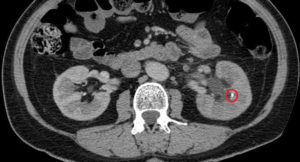

Основная почечная ткань довольно уязвима для различных неблагоприятных воздействий, поэтому оценка ее состояния помогает в диагностике. Наиболее распространенным и самым доступным методом исследования почек остается УЗИ. В некоторых случаях, когда нужна более подробная визуализация, назначается компьютерная или магнитно-резонансная томография.

С помощью перечисленных процедур возможно совершенно точно определить анатомические особенности, выявить отклонения толщины, обнаружить структурные изменения и повреждения. Любые изменения структуры паренхимы называют диффузными. Кроме того они могут быть очаговые, то есть расположенные на отдельных ее участках.

Ультразвуковая диагностика позволяет довольно точно визуализировать органы и обнаружить даже небольшие изменения в тканях. По степени визуализации они могут быть четкими и нечеткими, по выраженности – слабыми, умеренными и выраженными.

Почти все нарушения связаны с плотностью органов. Неспецифические структурные изменения в почках – это видимые на УЗИ результаты.

В основе этого метода диагностики лежит принцип эхолокации. На все ткани человеческого тела действуют ультразвуковые волны, которые каждый орган отражает по-разному.

Интенсивность ответа — эхогенность — зависит от его плотности, структуры. Черно-белое изображение монитора отражает эту плотность и многое говорит врачу о патологических изменениях.

Признаки опасного новообразования ничем не отличаются от доброкачественного. Для диагностики необходимы КТ и УЗИ. При поражении синуса опухоль легко обнаружить при пальпации.

УЗИ — основной метод, определяющий эхопризнаки расширения синусов и зоны с повышенной эхогенностью. Однако простой констатации факта бывает недостаточно, особенно это касается детей до 3 лет. Поэтому для подтверждения подозрений им назначают КТ. Также проводят другие исследования:

- КТ, МРТ — для выявления различных потенциальных новообразований;